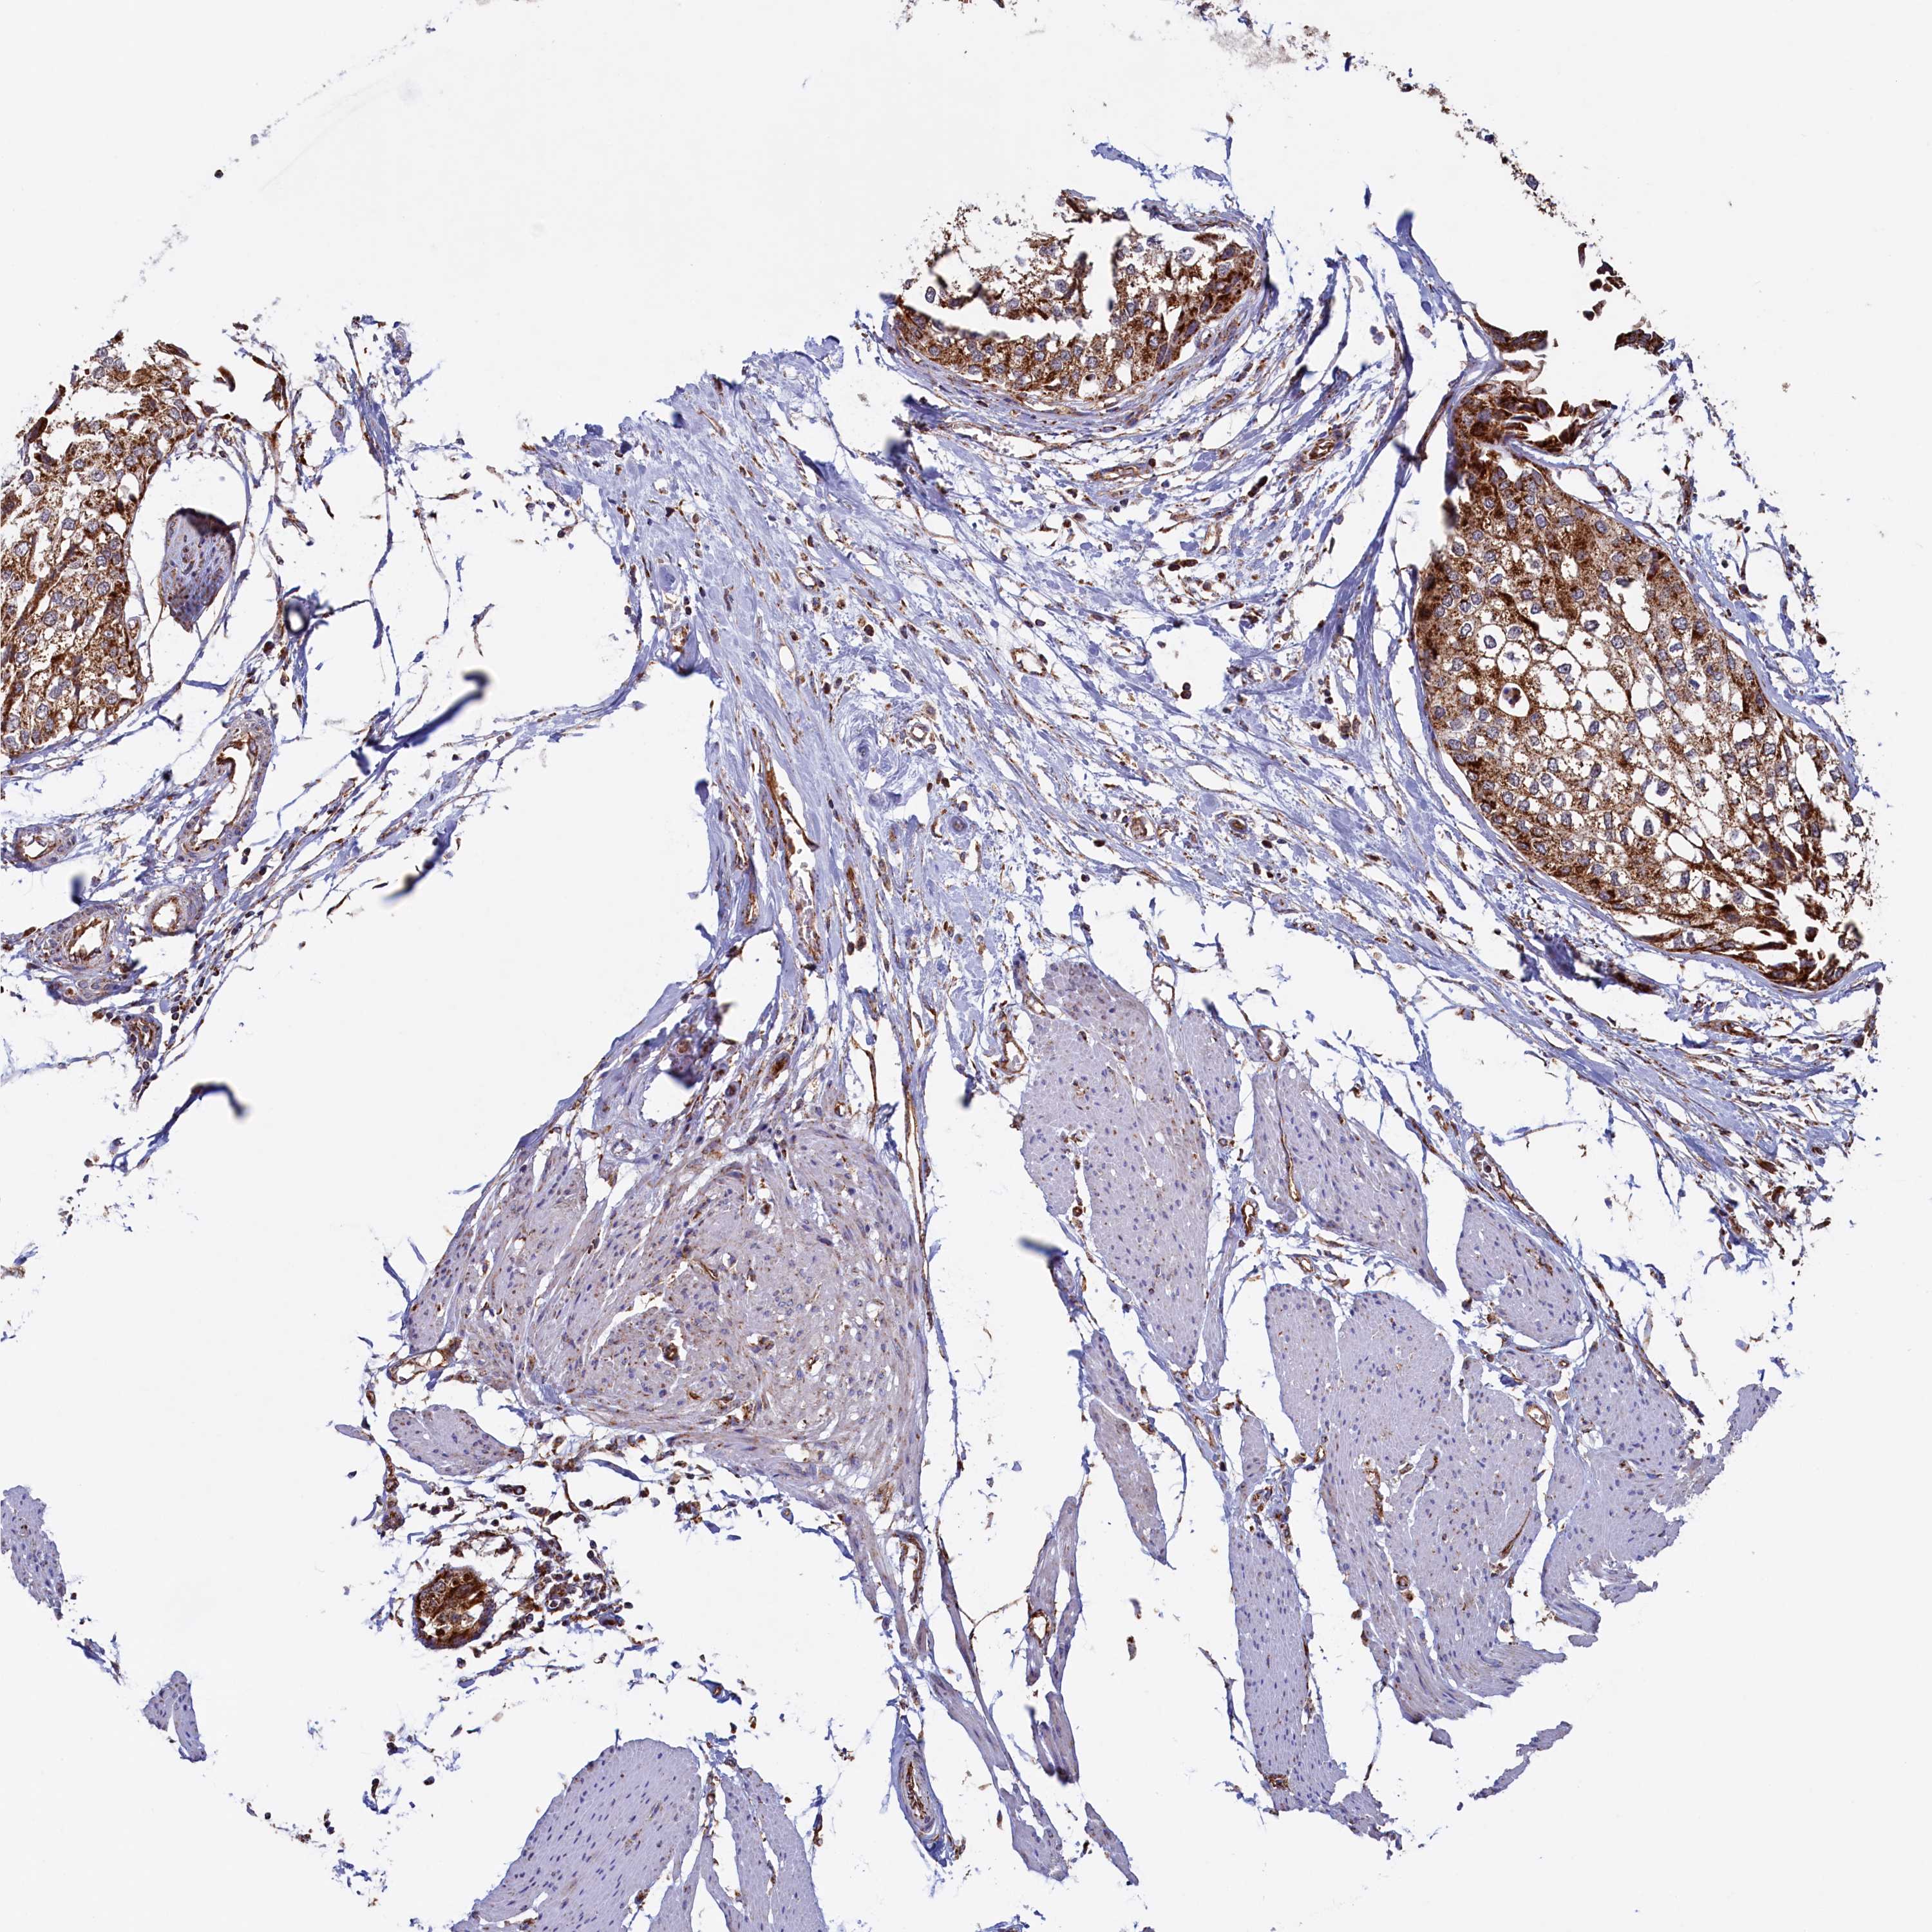

UROTHELIAL CANCER - Protein expressioni

A mouse-over function shows sample information and annotation data. Click on an image to view it in a full screen mode. Samples can be filtered based on level of antibody staining by selecting one or several of the following categories: high, medium, low and not detected. The assay and annotation is described here.

Note that samples used for immunohistochemistry by the Human Protein Atlas do not correspond to samples in the TCGA dataset.

Antibody stainingi

Antibody staining in the annotated cell types in the current human tissue is reported as not detected, low, medium, or high, based on conventional immunohistochemistry profiling in selected tissues. This score is based on the combination of the staining intensity and fraction of stained cells.

Each image is clickable and will lead to virtual microscopy that enables deeper exploration of all samples and also displays staining intensity scores, fraction scores and subcellular localization as well as patient and tissue information for each sample.

Antibody HPA041012

Staining

High

Medium

Low

Not detected

Intensity

Strong

Moderate

Weak

Negative

Quantity

>75%

75%-25%

<25%

None

Location

Nuclear

Cytoplasmic/membranous

Cytoplasmic/membranous,nuclear

Urothelial carcinoma, High grade

Urothelial carcinoma, Low grade